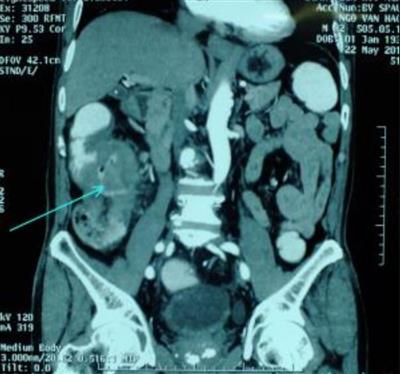

Làm thế nào để phát hiện ung thư đại tràng di căn sang gan?

Tôi là Huỳnh Công Dũng, 56 tuổi đã bị ung thư đại tràng 3 năm. Tôi có được biết ung thư đại tràng thường di căn sang gan. Các chuyên gia có thể cho tôi hỏi làm sao để biết mình có bị ung thư đại tràng di căn sang gan và biện pháp chữa trị như thế nào